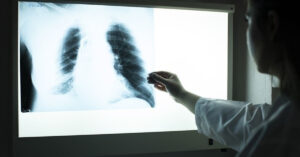

Kış aylarında artan solunum yolu enfeksiyonları arasında bocavirüs de yer almaya başladı. Uzmanlar, özellikle 2 yaş altı çocuklarda ağır zatürreye neden olabilen virüsün, hızlı nefes alma, öksürük ve ateş gibi belirtilerle kendini gösterdiğine dikkat çekiyor Havaların soğuk seyrettiği şu günlerde solunum yolu enfeksiyonları da artış gösteriyor. Önlem alınmaması durumunda ölüme...